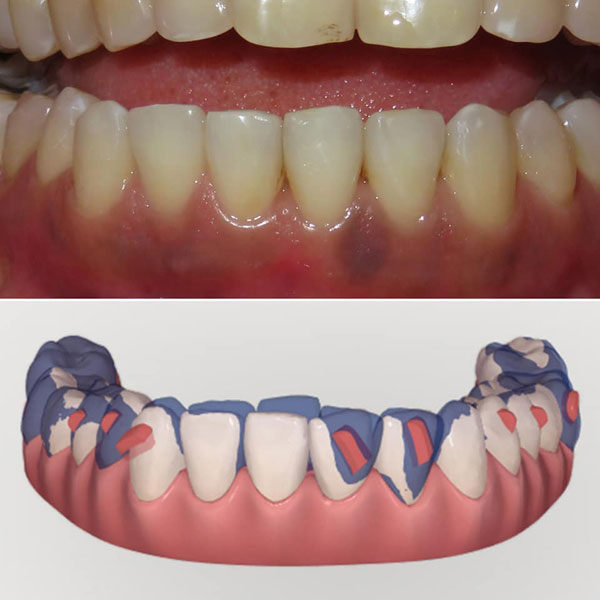

| Choice of obliquely placed conventional attachments |

| The superimposition |